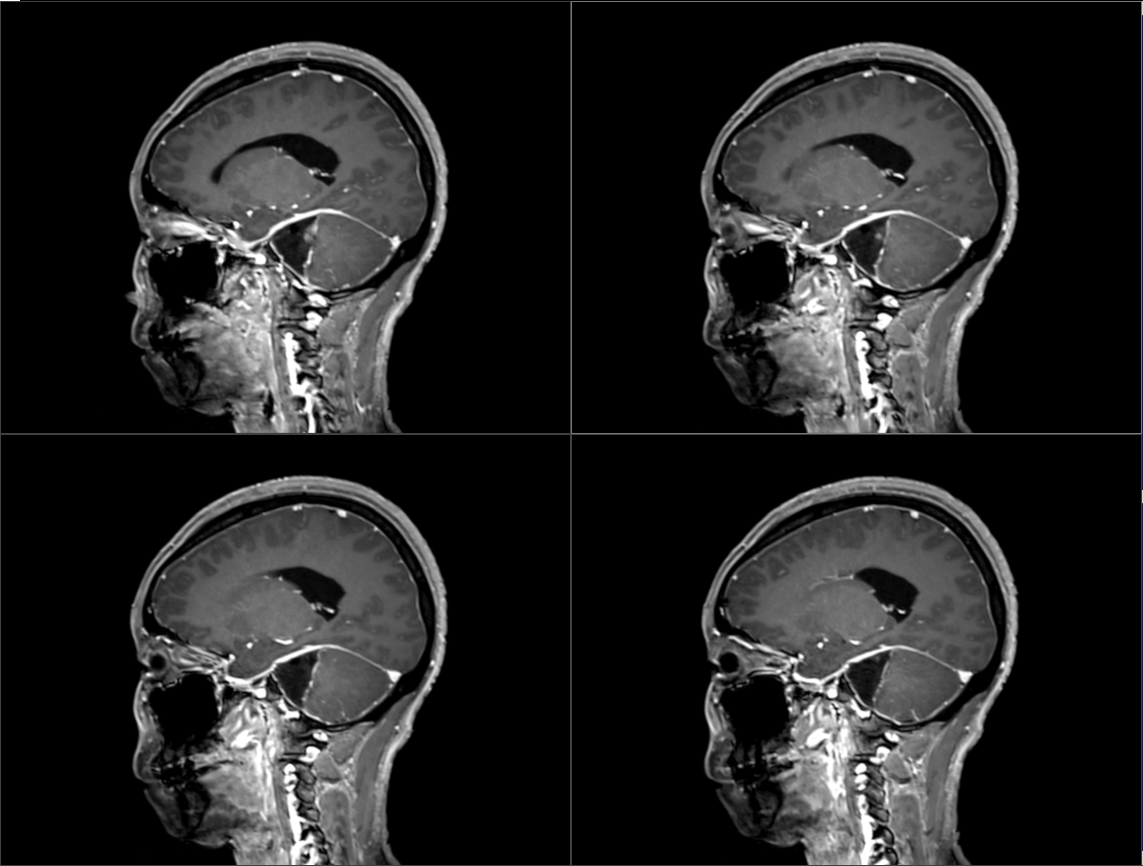

术前影像:

术后影像: